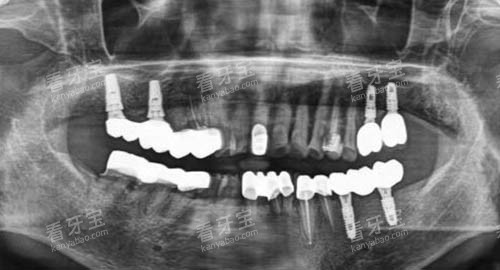

例如,智能化口腔全景机能够快速、比较准地拍摄口腔全景片,为医生的诊断提供详细的影像资料;较高的牙椅具备多种功能,能够根据患者的需求进行舒适的调整,让患者在诊疗过程中减少不适感。